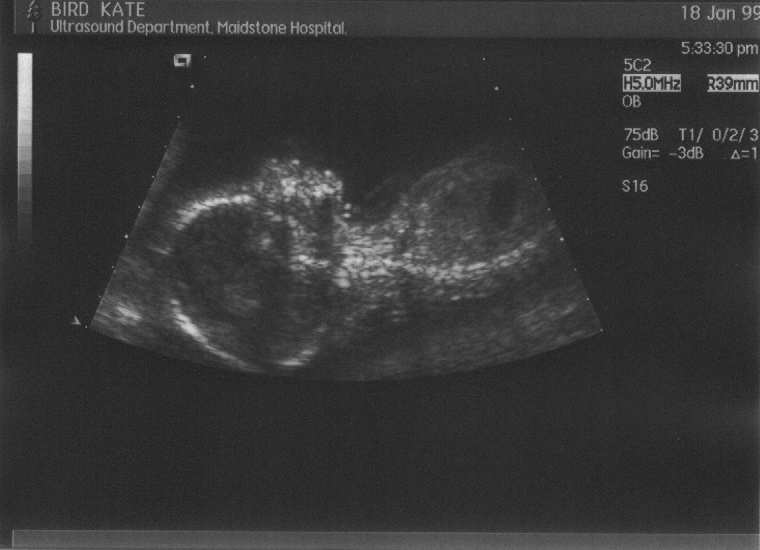

Pictures from the 37–week (& 6 days) stage in the Fœtal Assessment Unit. Check ’em out:

Week 37, scan 1  (hand covering face)